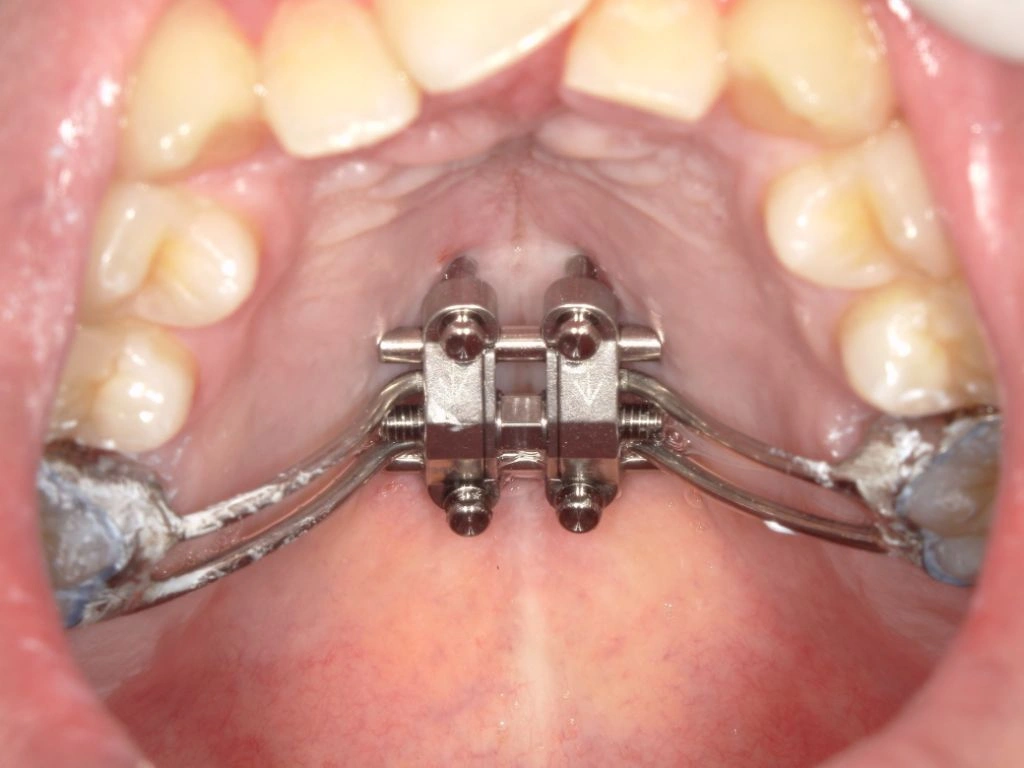

まず、MSEの中央部に正中口蓋縫合をまたぐ位置に4本の矯正用アンカーを埋入しました。浸潤麻酔で痛みなく、15分程度で処置自体は終了です。

中央部にネジを回す部分があるため、付属するレンチを患者さんに1日1回を目安に回していただきます。

初めは拡げる応力が集中するため、鈍痛を感じることもありますが、日常生活に大きな支障が出るほどではありません。

MSEの効果が出てくると、上顎の前歯部には隙間ができます。これは見た目としては我慢ポイントにはなるのですが、確実に正中口蓋縫合が離開して骨格的な拡大ができている証拠でもあるので不安になる必要はありません。